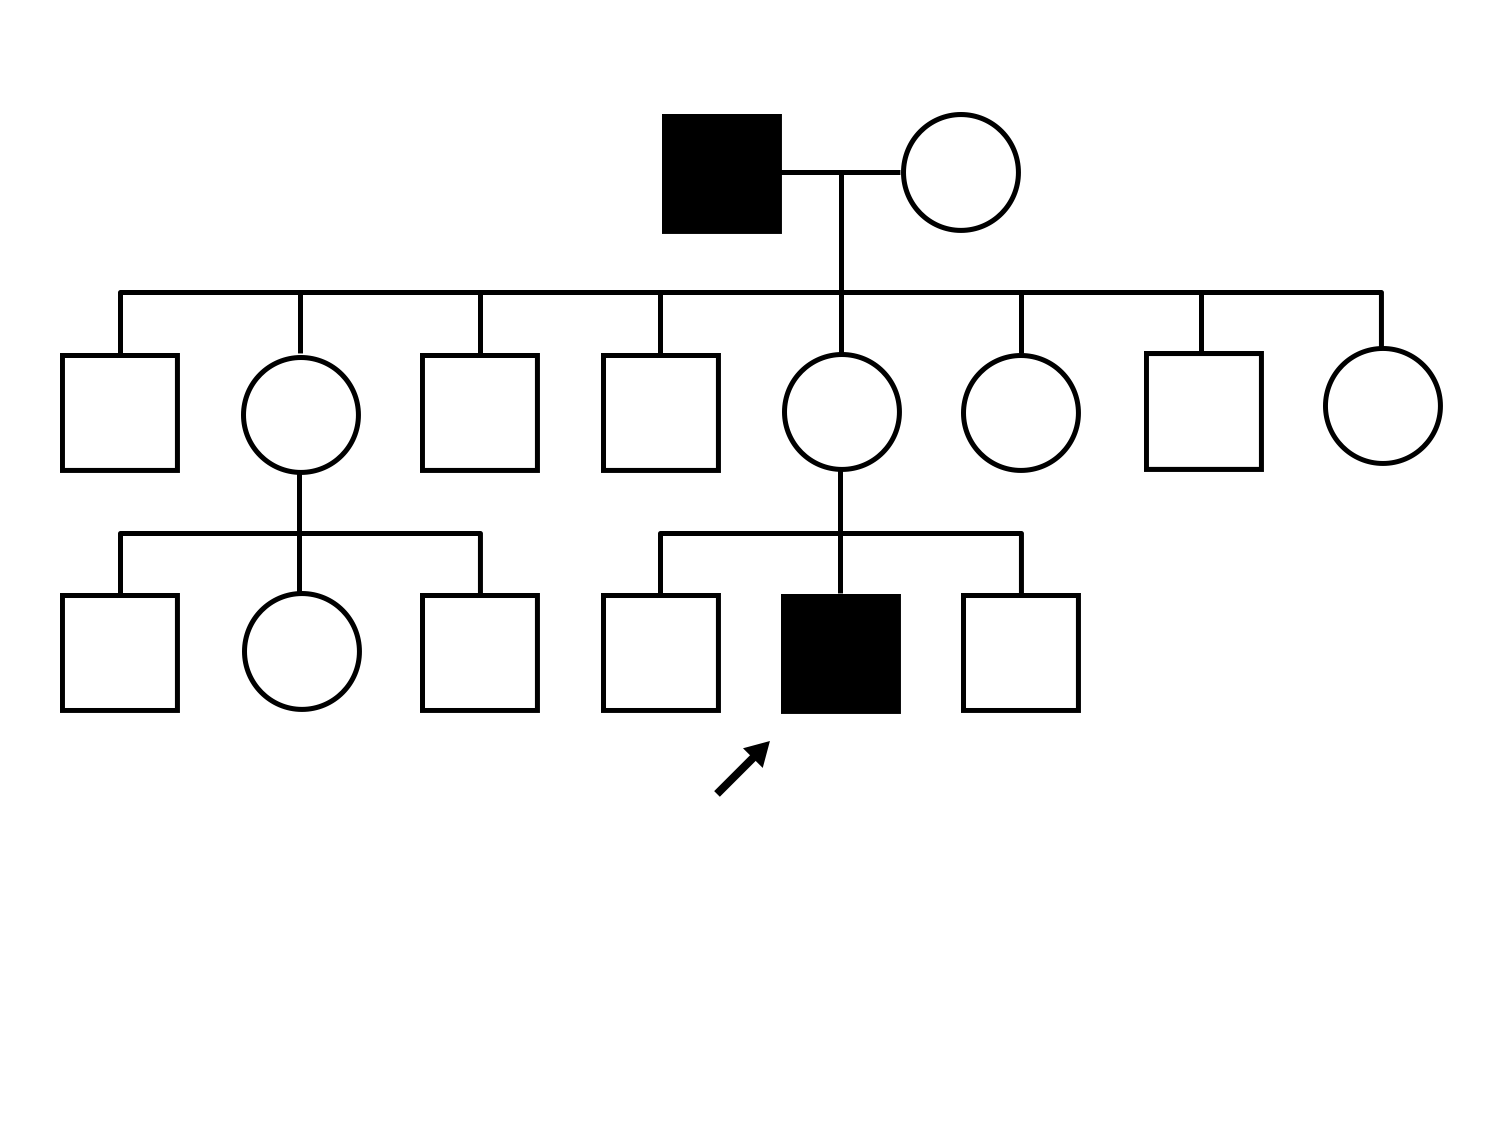

XL Cone and Cone Rod Dystrophy (IA1bi)

XL Cone and Cone Rod Dystrophy (IA1bi)

This 52 year old man had normal vision until his mid 30's when he began to have trouble distinguishing colors. the issuing 10 years he had a gradual loss of visual acuity accompanied by increasing photophobia.

| XL Cone and Cone Rod Dystrophy | RPGR | Gly1093 del2gGA | XL |